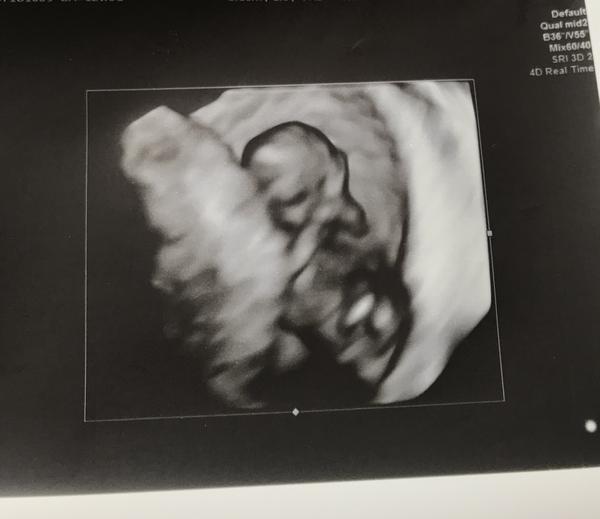

@zvedava_cica tak to vyzera ze je tam ✊

@zvedava_cica toto je určite tehu 😉Veľmi držím palce!